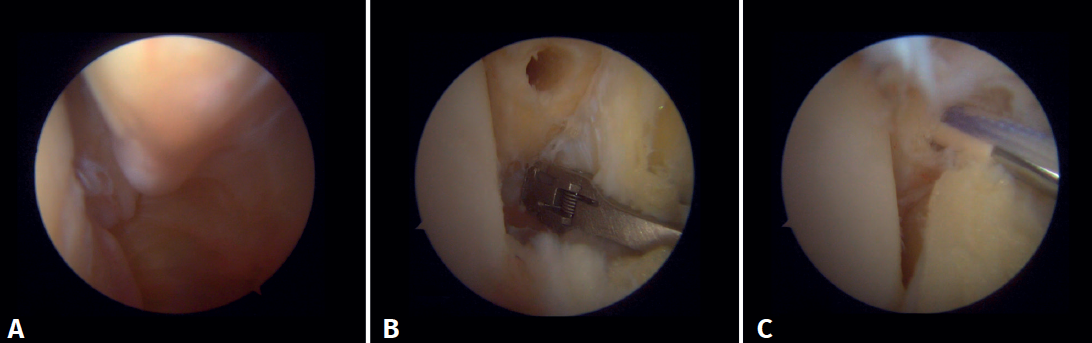

Anterior arthroscopic view

Twenty percent of the ATFL is intra-articular(7). On adopting an anteromedial access of the ankle, directing the arthroscope laterally, we can see the distal fibers of the ATFL with their oblique distribution and their continuation with the anterior talofibular ligament (Figure 2). If we move into the tibiotalar joint, we see the distal tibiofibular joint with the syndesmotic recess occupied by synovial tissue (Figure 3).

Posterior arthroscopic view

From the posterolateral approach we identify the lateral (fibular) malleolus and, from here, we visualize the intra-articular fibers of the PTFL, which run obliquely and insert into the distal portion of the tibia. We also see the distal thickening of the PTFL (transverse ligament) in continuity with the posterior lip of the distal tibia (Figure 4).

Arthroscopic evaluation of the syndesmosis

From the anteromedial portal we can directly visualize the distal fibers of the ATFL. Disinsertion of these fibers does not always result in instability of the syndesmosis, but it does require us to check it. In our experience, we prefer assessment of the coronal plane of the syndesmosis. We introduce the arthroscope into the tibiotalar joint directing the camera cranially. In this way we have a direct view of the distal tibiofibular joint. We then assess stability by attempting to insert the palpation probe into the joint. If it is possible to do so, we classify the syndesmosis injury as unstable (Figure 6A).